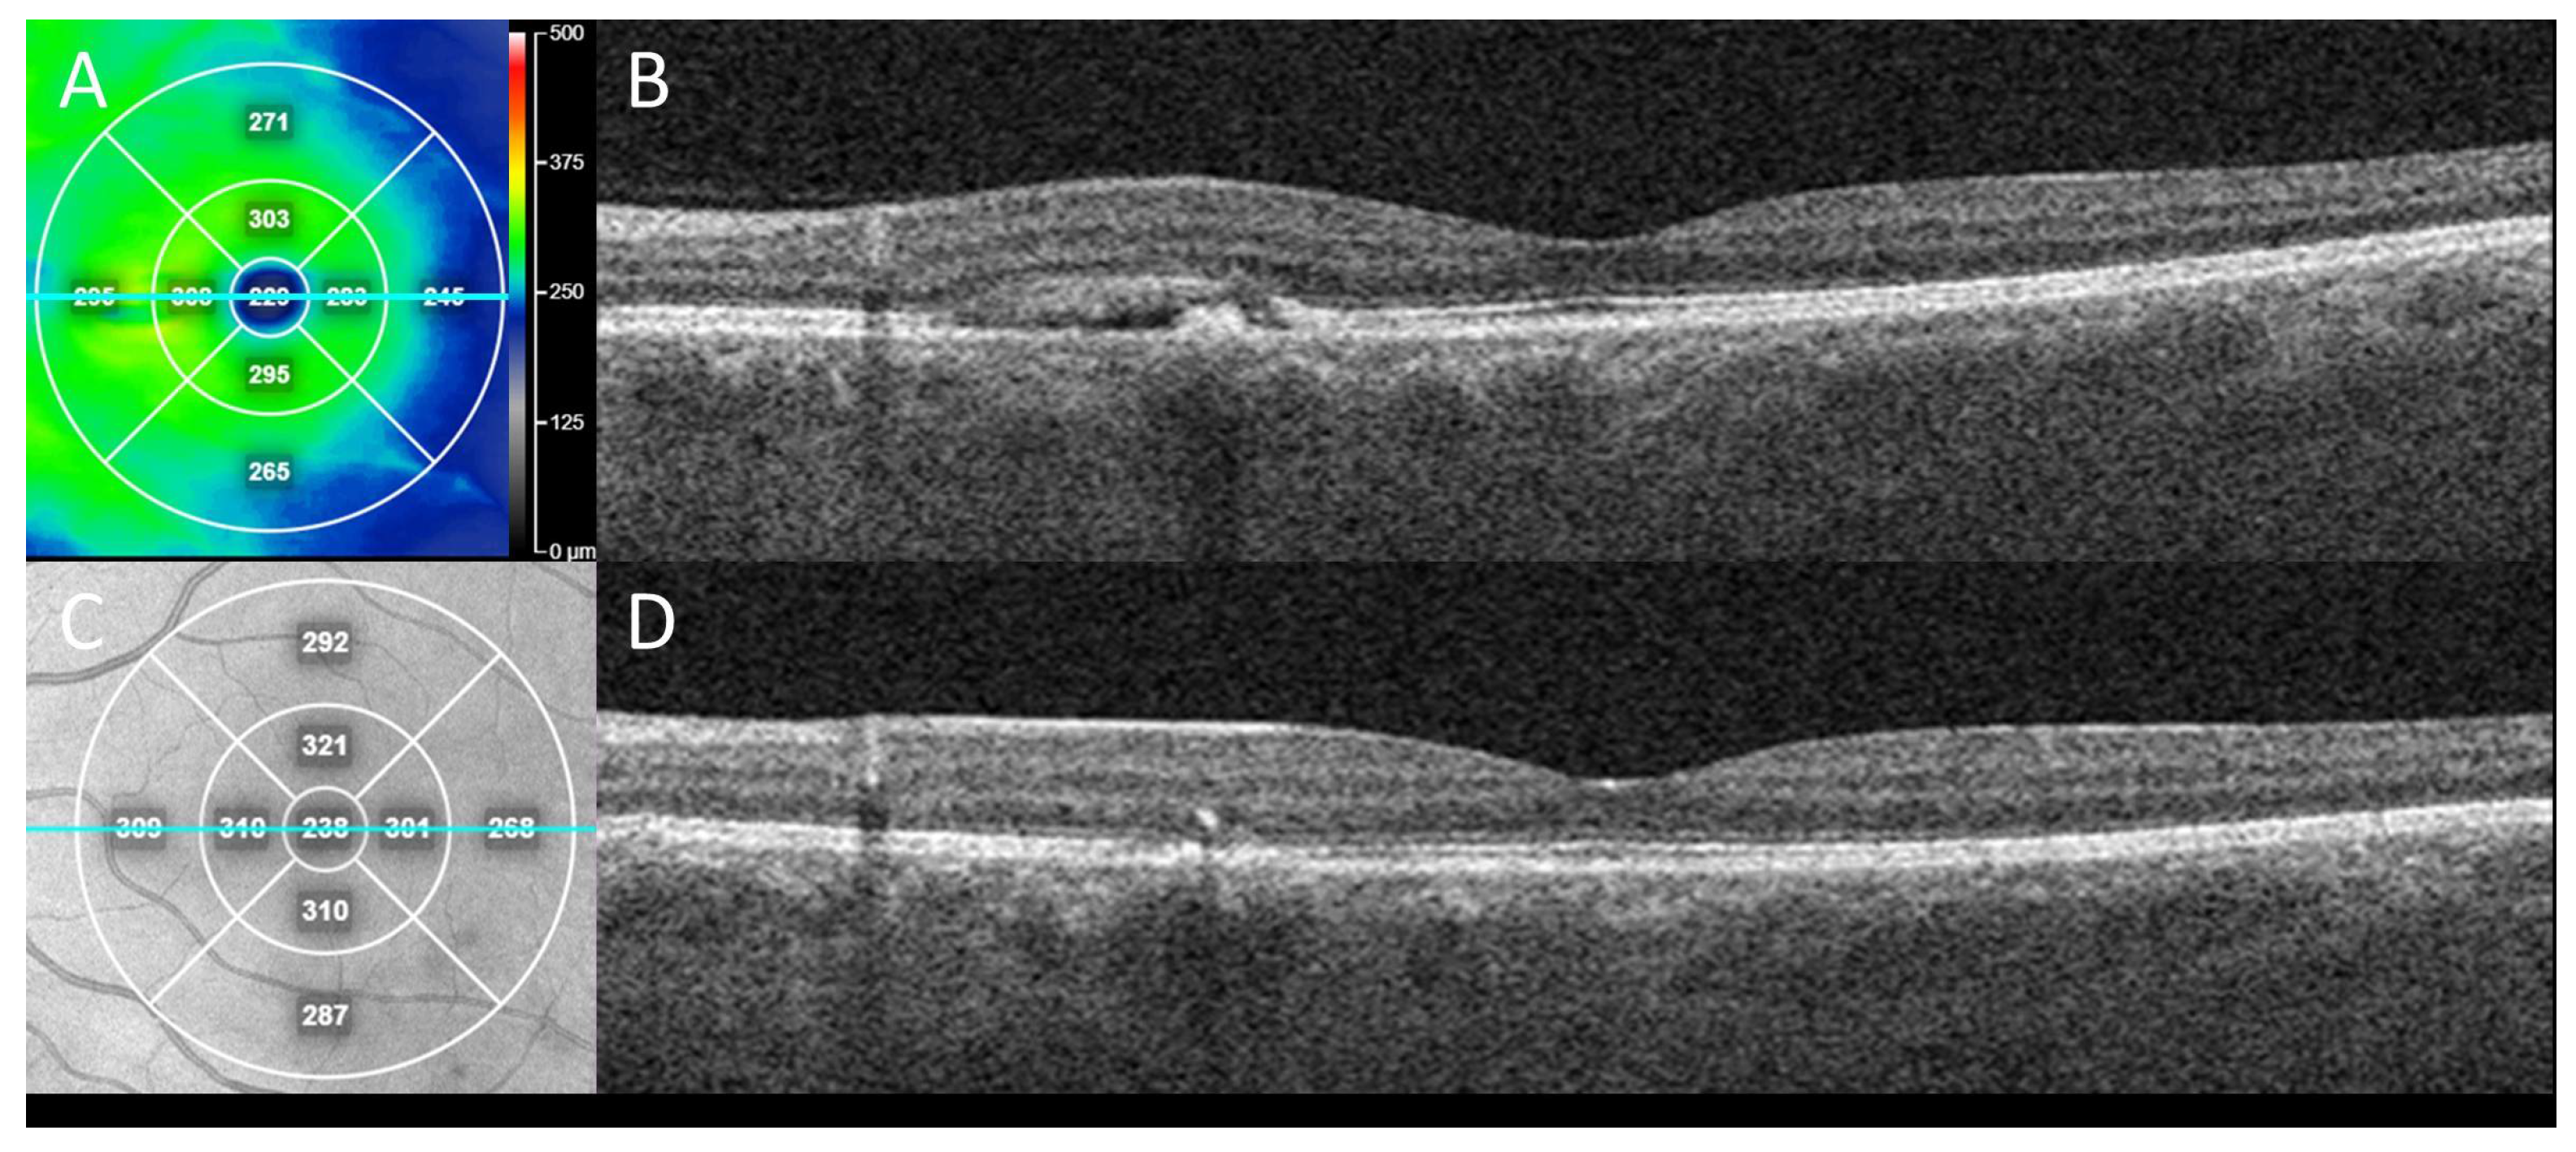

Figure 2.

Clinical outcome from case in Figure 1 following treatment for CSCR with secondary neovascularization. En face swept-source OCT “heat” thickness map (A) with corresponding line (teal) OCT B-scan indicates subretinal fluid with RPE detachment in nasal macula of left eye at presentation (B) which alone could be mistaken for CSCR without neovascularization. This eye was treated with two sequential, intravitreal anti-vascular endothelial growth factor (VEGF) injections (bevacizumab), one month apart. Three months after initial presentation, en face near-infrared reflectance (C) with corresponding line (teal) OCT B-scan demonstrated sustained resolution of the subretinal fluid and collapse of the RPE detachment (D), consistent with response of exudation and neovascularization to anti-VEGF treatment.